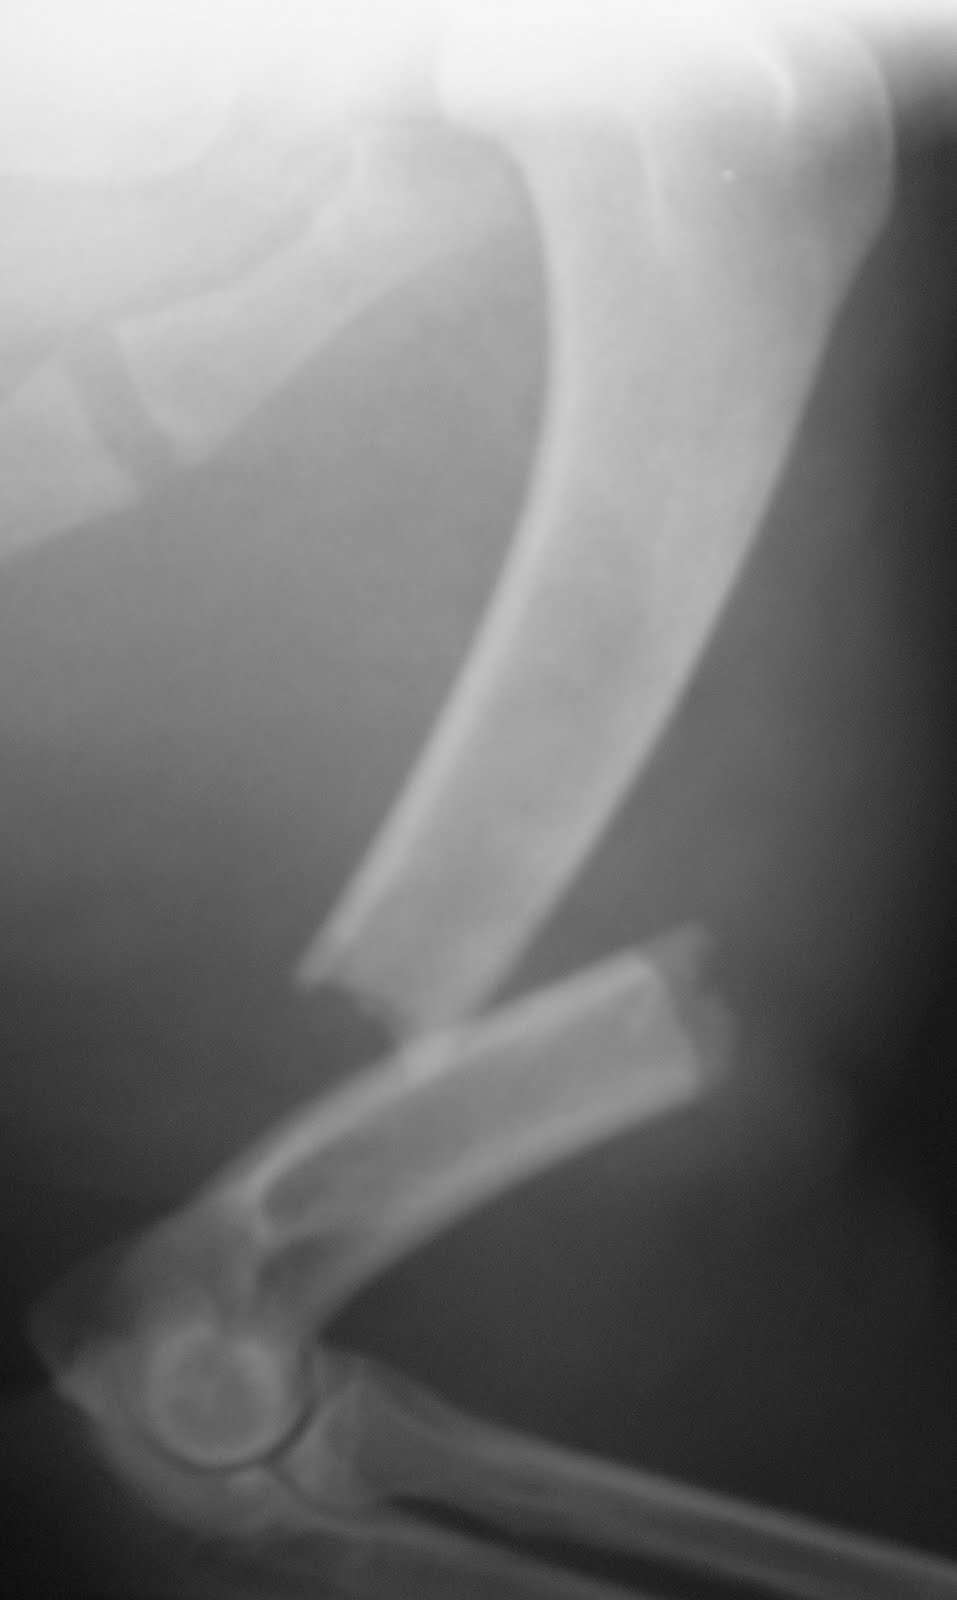

Ορθοπεδικά περιστατικά πριν & μετά: κάταγμα βραχιονίου οστού

Ο σκύλος της φωτογραφίας προσκομίστηκε στο Κτηνιατρικό Κέντρο Ιλισίων με αδυναμία στήριξης στο πρόσθιο δεξιό άκρο μετά από τροχαίο ατύχημα. Μετά από ορθοπεδική εξέταση και ακτινογράφηση διαπιστώθηκε κάταγμα βραχιονίου οστού. Έγινε οστεοσύνθεση με μεταλλική πλάκα.

Ακτινογραφία εγκάρσιου κατάγματος διάφυσης βραχιονίου σκύλουΟ σκύλος μετά την ορθοπεδική χειρουργική επέμβαση οστεοσύνθεσης κατάγματος βραχιονίουΑκτινογραφία βραχιονίου μετά την οστεοσύνθεση με μεταλλική πλάκα και κοχλίες